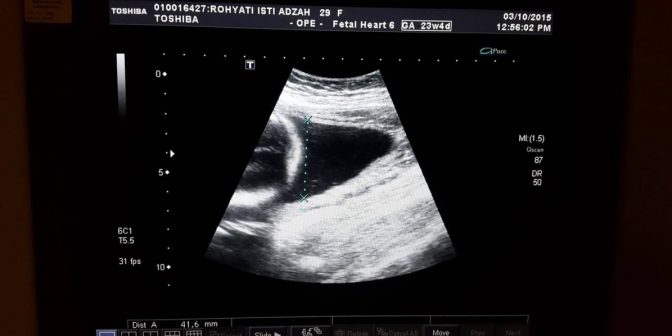

Metode USG (Ultrasonography)

Tes ini merupakan tes yang sangat terkenal dikalangan ibu hamil. Tes ini biasanya dilakukan secara rutin sejak umur janin sekitar 18 atau 22 minggu.

Tes ini dilakukan untuk mengetahui dan melihat anatomi sang bayi dan memastikan bahwa semua bagian tubuh bayi bisa tumbuh dengan baik setiap waktu. Sehingga, melalui tes ini, dokter bisa mengetahui apa jenis kelamin bayi.

Sayangnya, USG (Ultrasonography) ini memiliki keakuratan yang tidak lebih baik dari CVS atau Amniosintesis. Terkadang, dokter bahkan bisa terkecoh saat melakukan tes USG.

Tesnya membutuhkan kemampuan penglihatan untuk melihat kondisi dalam kandungan, bisa saja bentuk jenis kelamin yang dilihat bukanlah kelamin yang sebenarnya. Misalnya kekeliruan melihat tali pusar yang dikira adalah jenis kelamin laki-laki.